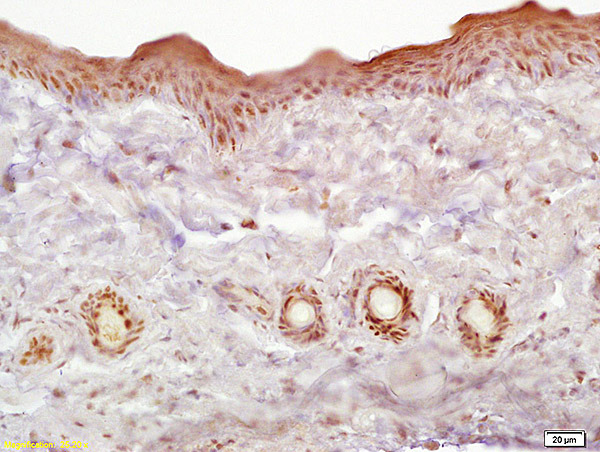

- Main image

- Experimental details

- Formalin-fixed and paraffin embedded rat skin labeled with Anti-Galectin 7 Polyclonal Antibody, Unconjugated (bs-5809R) at 1:200 followed by conjugation to the secondary antibody and DAB staining

- Sample type

- Other comments

- Skin